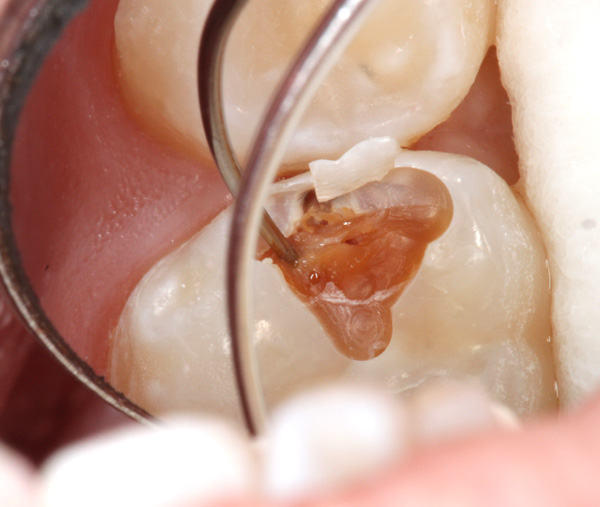

Aufgebohrt ergeben sich dann die folgenden Situationen und der Umfang der Approximalkaries wird deutlich:

Weiter eröffnet:

Hier kann man deutlich erkennen, dass das Dentin erweicht ist: